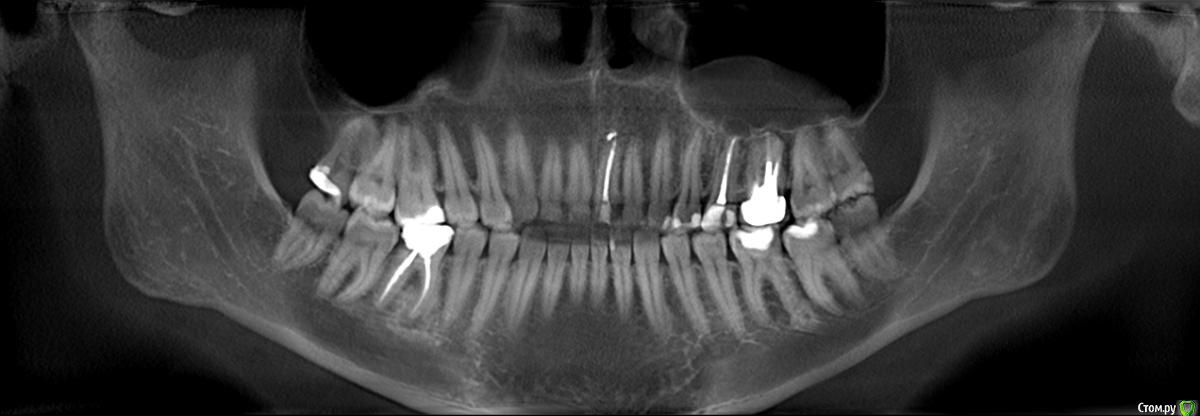

Олеся2018 Опубликовано 30 июня, 2018 Поделиться Опубликовано 30 июня, 2018 Добрый день! Необходим совет по поводу 25 и 26 зубов. На обоих кисты образовались после проведенного лечения. Болят уже два года... Проблема еще в том, что живу я на Чукотке, в одном из маленьких поселков, где нет нормальной медицинской помощи, а уж тем более стоматолога (до ближайшего врача-стоматолога полтора часа лёта на самолёте и не многие могут это себе позволить). Попасть к стоматологу можно только в очередном отпуске, который бывает раз в два года. В общем-то два года назад и был пролечен 25 зуб, а на 26-й поставлена коронка. Проблемы начались как только я вернулась домой из отпуска. Постоянная боль в 25-ом зубе и пульсация вокруг него, начал шататься. Так как у нас стоматолога нет, пришлось терпеть два года до следующего отпуска... Сейчас нахожусь на "материке", сделала снимки и КТ, и бегом к стоматологу на консультацию. Первый сказал, что только удаление зубов может помочь, второй стоматолог посоветовал заново пролечить каналы и посмотреть, что будет, третий отправил в челюстно-лицевую хирургию для удаления кист на 25-ом и 26-ом зубе с помощью резекции верхушек корней. Времени у меня всего месяц, дальше отпуск заканчивается и я возвращаюсь домой.Что нужно сделать, чтобы избавиться от кист с наибольшей вероятностью? Я готова и удалить эти зубы, лишь бы не было воспаления и постоянных болей. Еще два года мучений я не выдержу. Ссылка на комментарий

red_butler Опубликовано 1 июля, 2018 Поделиться Опубликовано 1 июля, 2018 кисты нет, есть периодонтит пятого зуба. Требуется его повторное лечение. Шестой - нужно "крутить" Кт Ссылка на комментарий

red_butler Опубликовано 1 июля, 2018 Поделиться Опубликовано 1 июля, 2018 Не знаю, правильно или неправильно все отлично, шестой тоже периодонтит. С ним сложнее, требуется снятие коронки и извлечение вкладки с последующим лечением каналов. Или замена на имплант Ссылка на комментарий

Олеся2018 Опубликовано 2 июля, 2018 Автор Поделиться Опубликовано 2 июля, 2018 шестой тоже периодонтит Стоматолог на всякий случай направил на консультацию в областную больницу к челюстно-лицевому хирургу. Сегодня была на приеме... Врач посмотрела КТ и сказала, что необходимо оперировать под общим наркозом, удалять кисты на 25 и 26 зубах и делать последующую гайморотомию, так как киста проросла в гайморову пазуху. Я, если честно, в шоке. Ссылка на комментарий

DmitrySH Опубликовано 3 июля, 2018 Поделиться Опубликовано 3 июля, 2018 С зубом 25 особых сложностей не должно быть. 26 под вопросом. Скорее всего большой дефицит тканей зуба уже имеется, после извлечения вкладки совсем мало от зуба останется. Возникает вопрос не в самом лечении, а дальнейшей перспективе данного зуба.46, обратите внимание, на снимке тоже гранулема. Ссылка на комментарий

Олеся2018 Опубликовано 6 июля, 2018 Автор Поделиться Опубликовано 6 июля, 2018 25 перелечили, остается только ждать, уменьшится воспаление или всё останется на месте. 46, обратите внимание, на снимке тоже гранулема. 46 он тоже проблемный, там под пломбой видно, что зуб темно-серого цвета, корней скорее всего для коронки не хватит.(( Ссылка на комментарий